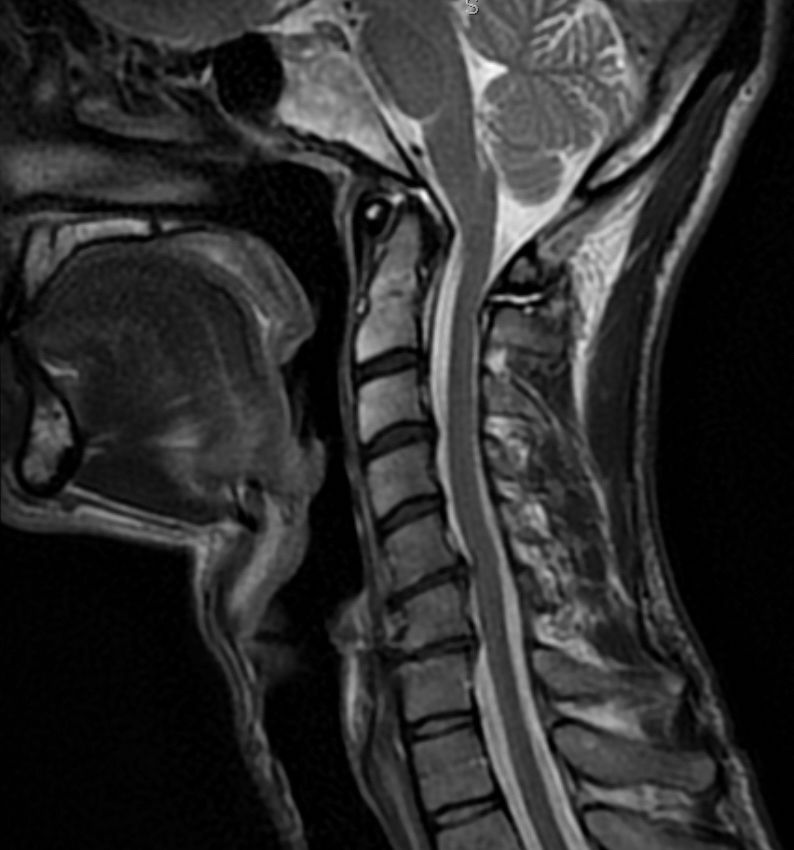

Post image

I have been experiencing intensifying radiculopathy lately… and an MRI yesterday revealed that I have significant cervical disc degeneration that is likely the cause. :-/

18.04.2025 21:15 — 👍 0    🔁 0    💬 0    📌 0